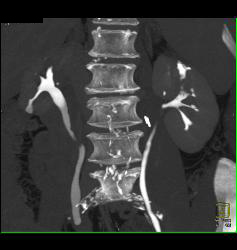

Transitional Cell Cancer (TCC) of Left Kidney- See CT Urogram and Full Sequence of Images